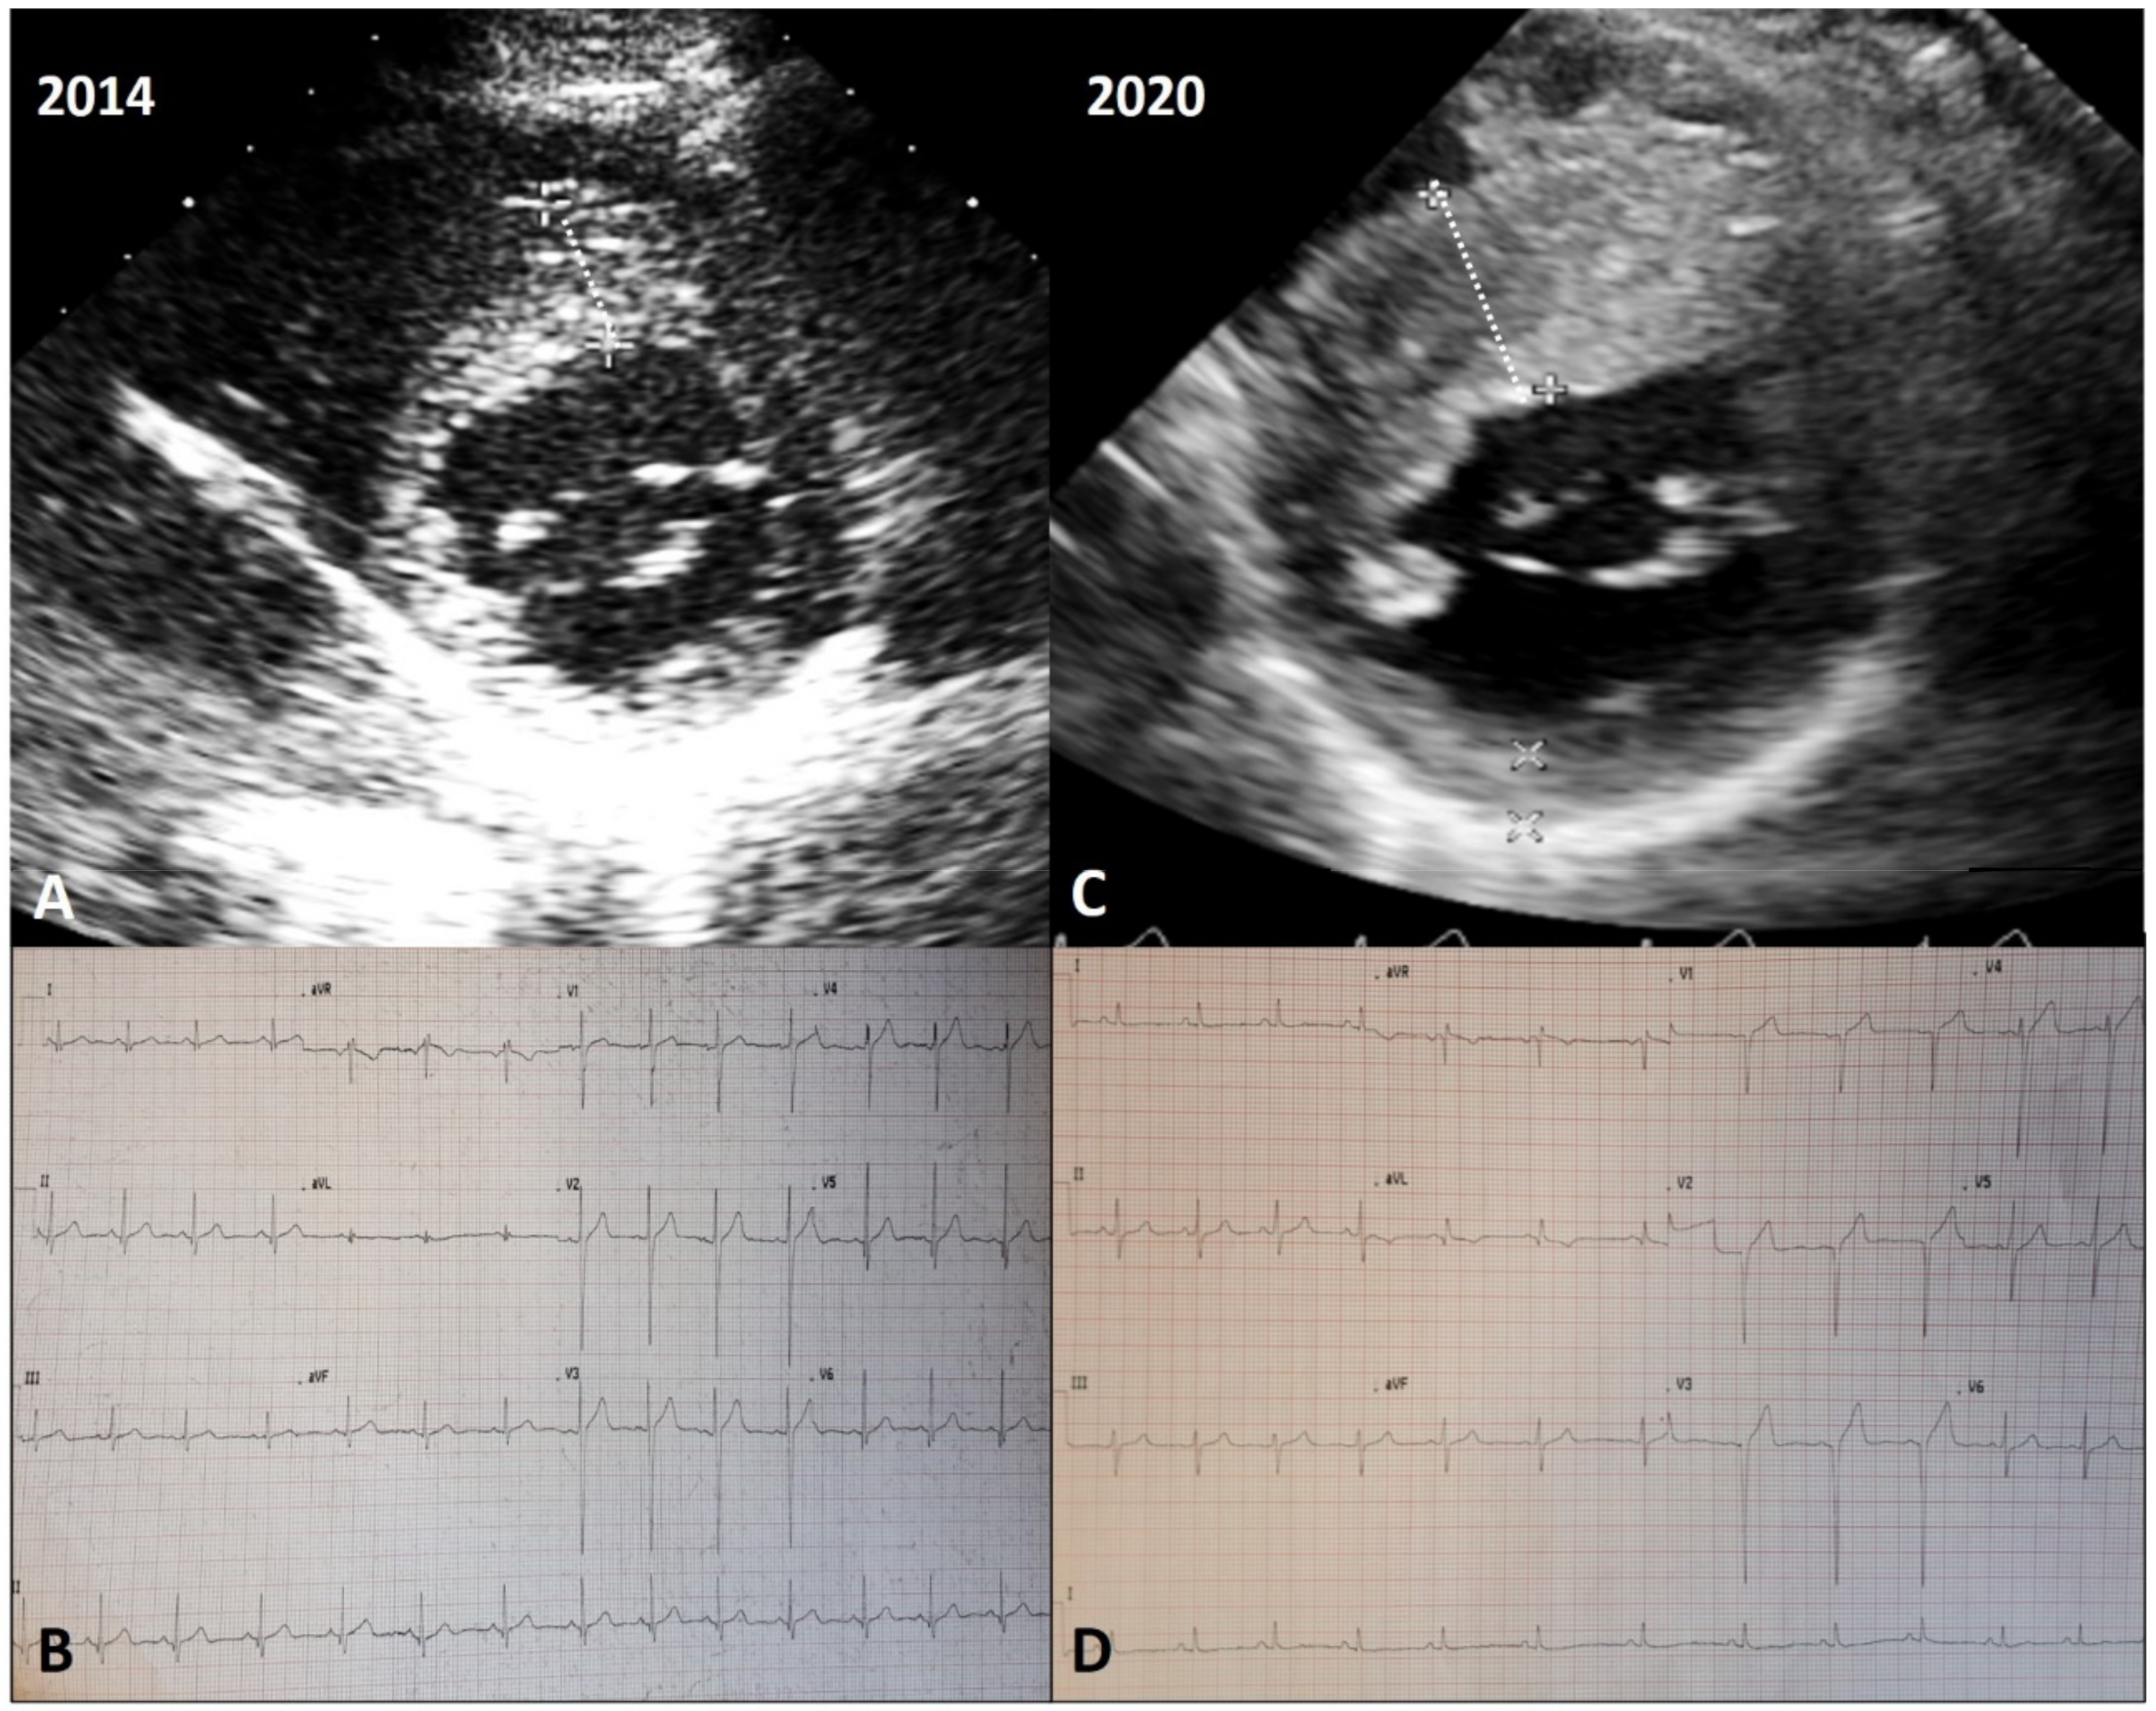

- Pennacchini, E.; Musumeci, M.B.; Conte, M.R.; Stöllberger, C.; Formisano, F.; Bongioanni, S.; Francia, P.; Volpe, M.; Autore, C. Electrocardiographic evolution in patients with hypertrophic cardiomyopathy who develop a left ventricular apical aneurysm. J. Electrocardiol. 2015, 48, 818–825. [Google Scholar] [CrossRef] [PubMed]